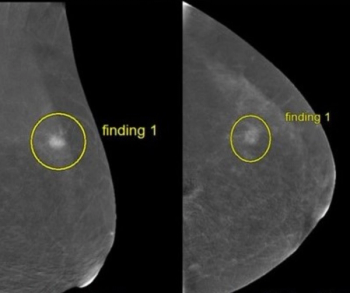

In multiple mammography datasets with the original radiologist-detected abnormality removed, deep learning detection of breast cancer had an average area under the curve (AUC) of 87 percent and an accuracy rate of 83 percent, according to research presented at the recent Society for Imaging Informatics in Medicine (SIIM) conference.